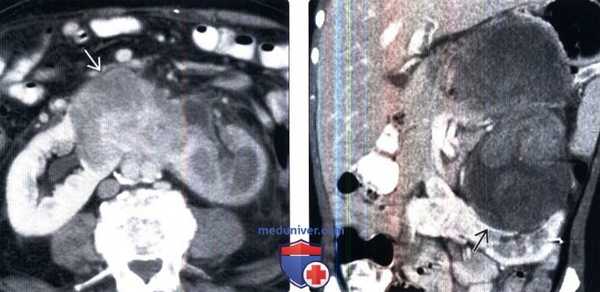

4. УЗИ:

• Исследование в режиме серой шкалы:

о Перешеек расположен впереди от позвоночника и прилегает к нижним полюсам противоположных почек

о Нижние полюса имеют изогнутую конфигурацию, а также удлиненные и плохо определяемые

о Форма перевернутого треугольника или грушевидная форма (продольное сканирование)

(Слева) Подковообразная почка. Нижние полюсы почек медиально отклонены, по срединной линии - перешеек. Питающие артерии, как правило, отходят от аорты или подвздошных артерий.

(Справа) Переднемедиальная ориентация лоханок может указывать на подковообразную почку. Тщательное сканирование по срединной линии позволяет даже во II триместре кпереди от аорты обнаружить паренхиматозную перемычку между почками.

2. УЗИ при подковообразной почке у плода:

• УЗИ в режиме серой шкалы:

о Нижние полюсы почек соединены перешейком:

- Перешеек может быть паренхиматозным или фиброзным

- Нижние полюсы ориентированы медиально

о Зачастую поворот не завершен:

- В 97% случаев почечная лоханка лежит вентральнее паренхимы

- Находят ориентированность почечной лоханки кпереди

о Почки низко расположены

о Почка изогнута по длинной оси

о Нижний полюс заострен или удлинен:

- Нижний край почки визуализируется с трудом

о Сращение верхних полюсов встречается редко:

- Почка имеет форму перевернутой подковы или пончика

о Может сочетаться с обструкцией лоханочно-мочеточникового сегмента:

- Оценивают, сохранена ли характерная коническая форма почечной лоханки

- Мочеточник не расширен